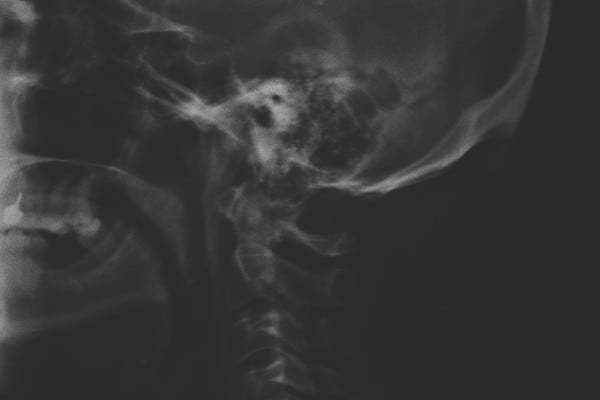

Các nhà nghiên cứu đã chụp tia X 218 với người trưởng thành trong độ tuổi từ 18 tới 30. Kết quả cho thấy, 41% trong số này có hiện tượng phát triển xương bất thường tại vị trí cổ.

| Cổ bị cong do sử dụng smartphone quá nhiều |